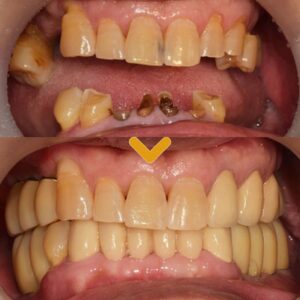

27. 수암동치과 교합 균형이 무너진 상태라면

수암동치과 교합 균형이 무너진 상태라면 [목차] ✔️ 초진 구강 상태와 치아 상실 확인 ✔️ 치료 방향 설정과 신경치료 진행 ✔️ 임플란트 식립 및 뼈유착 과정 ✔️ 보철 수복과 교합…